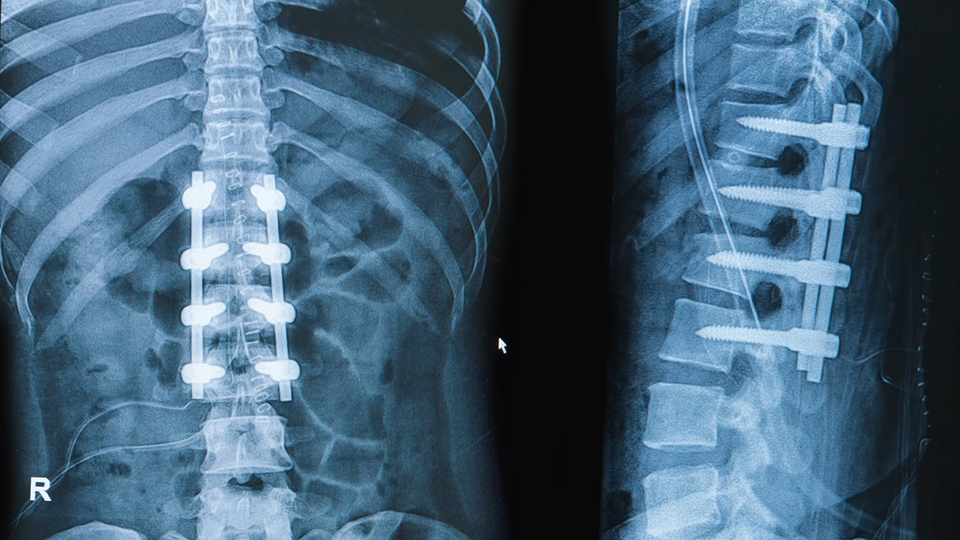

"В тот же день сотрудники полиции прибыли по месту жительства злоумышленника. Постучав в дверь, сотрудники правоохранительного органа потребовали, чтобы мужчина открыл. Осознавая причину появления полицейских, молодой человек выпрыгнул из окна своей квартиры, расположенной на четвертом этаже. В результате падения с высоты он получил перелом позвоночника. В настоящее время его лечение завершилось выздоровлением", – сообщает ведомство.